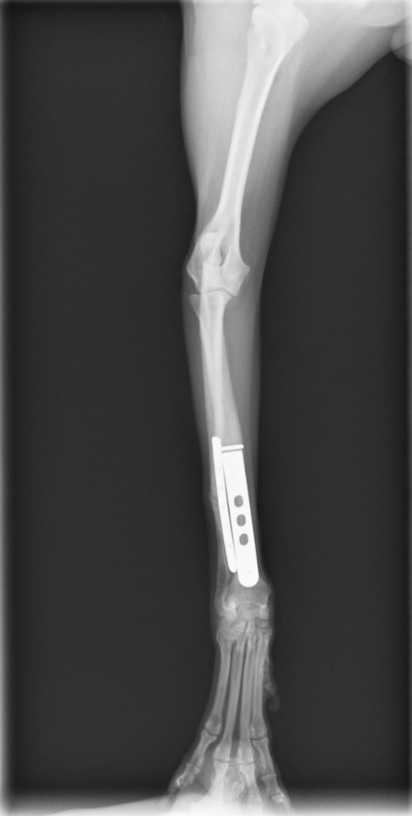

今回のワンちゃんも手術の決断をしてくださり、無事骨折した骨は、元通りのまっすぐな足の角度に治りました!

骨折の手術で大きな問題となるのは、癒合不全という、一見くっついているように見えるが、骨としての機能が損なわれてしまいずっと歩けないという状況です。不幸にも足を切らないといけないほどの状況まで行ってしまう子も中にはいるかもしれません。

当グループの骨折手術は初回手術(1回目の手術のこと)であれば100%治っております。他の病院で一度手術してから再手術の場合、すでに癒合不全が起こっていると当然手術は難しくなります。癒合不全の手術は1回で治らないこともあります。